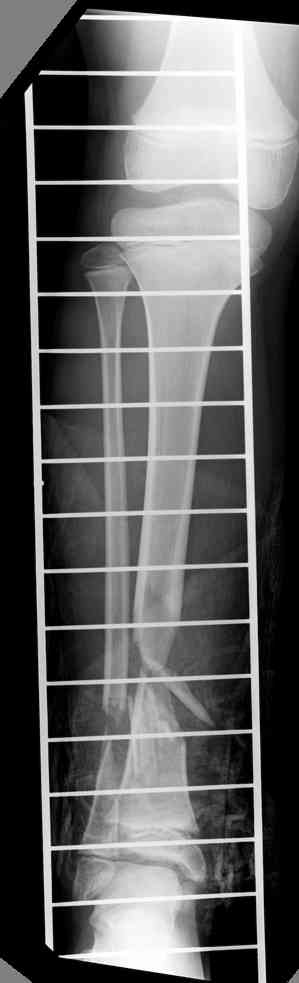

1 - рентгенограмма (прошу прощения за качество) при поступлении;

Произведено ПХО, acute shortening (5 см), фиксация стержневым аппаратом Hoffman.

3,4 - через 4 недели наложен спице-стержневой аппарат, произведена остеотомия большеберцовой кости в верхней трети, раны зажили, проводилась дистракция в аппарате.

5, 6 - через 2,5 мес после травмы выполнен закрытый остеосинтез блокируемым штифтом.

7, 8, 9, 10, 11 - через 8 мес после травмы перелом сросся.